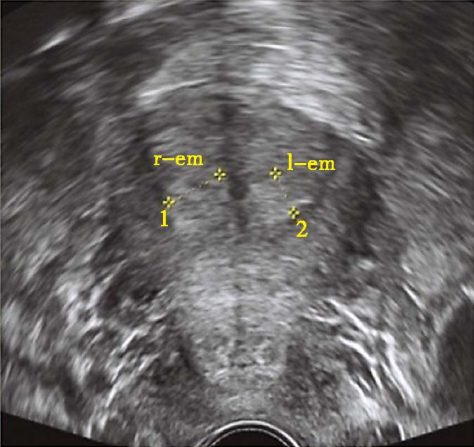

先天性无子宫经腹部超声

先天性无子宫经阴道超声

始基子宫二维超声

始基子宫三维超声